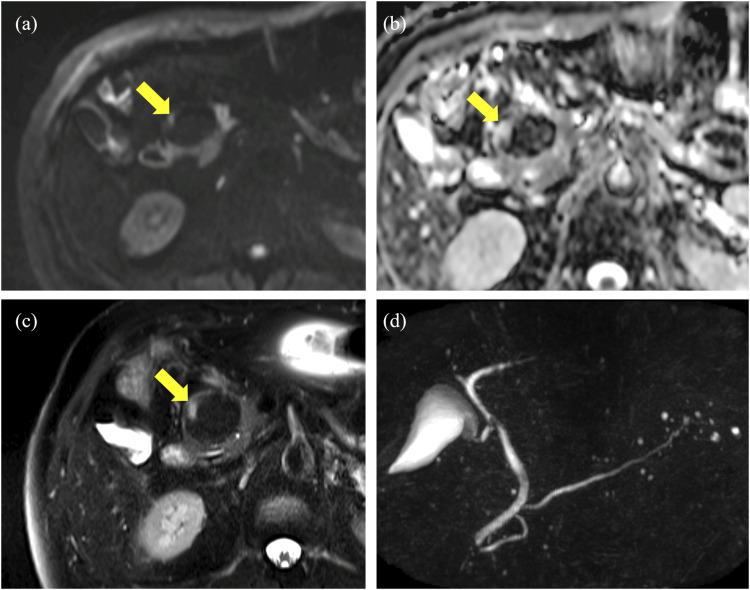

胰腺脂肪瘤性假性肥厚(LPH)是一种罕见疾病,在这种疾病中,胰腺实质被成熟的脂肪组织取代。这是一种特发性疾病,其诊断依据是组织病理学分析。在此,我们报告了一例 50 岁男性患者的病例,他在计算机断层扫描中发现胰腺头部有脂肪瘤肿块,仔细检查后发现是肾肿瘤。我们怀疑是脂肪肉瘤,于是进行了开腹手术。然而,组织学分析却显示为 LPH。LPH的几种成像结果可以实现无创诊断,并有助于临床治疗。

Lipomatous pseudohypertrophy of the pancreas (LPH) is a rare disease in which the pancreatic parenchyma is replaced with mature adipose tissue. It is an idiopathic condition whose diagnosis is made based on histopathological analyses. Herein, we report the case of a 50-year-old male patient with a lipomatous mass in the head of the pancreas on computed tomography for close examination of a renal tumor. We suspected liposarcoma, and laparotomy was performed. However, histological analyses revealed LPH. Several imaging findings of LPH can enable a noninvasive diagnosis and help its clinical approach.